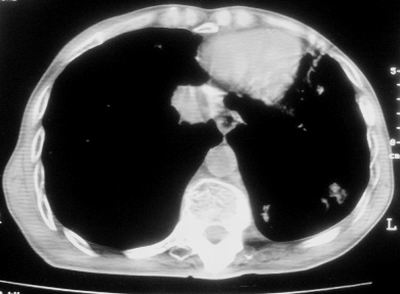

标题: CT11864:男,47岁,反复咳嗽、咯痰、咯血3年,请分析. [打印本页]

患者,男,47岁,反复咳嗽、咯痰、咯血3年,再发5天。痰培养未找到真菌、抗酸杆菌、癌细胞。

左肺上叶体积明显缩小,其内见多发透光区,纵隔向左侧移位,左肺下叶多发班片状病灶,边界模糊,1左肺上叶先天肺发育不全,2左肺下叶肺炎,

左肺上叶结核伴肺纤维化,纵隔移位,左肺下叶感染性病变,建议抗炎抗结核后复查,双肺气肿.

以下是引用xulianj在2008-2-25 21:01:00的发言:[br]左肺上叶结核伴肺纤维化有霉菌球形成,纵隔移位,左肺下叶感染性病变,建议抗炎抗结核后复查,双肺气肿.

考虑:左肺慢纤伴霉菌球形成、双肺全小叶型肺气肿。

1)考虑为:左肺上叶肺结核(空洞形成),伴左下肺感染;不排除霉菌感染可能。2)肺气肿。

左肺上叶结核伴肺纤维化空洞形成并左肺下叶感染,纵隔牵拉移位,建议作进一步检查排除左侧肺霉菌感染可能。